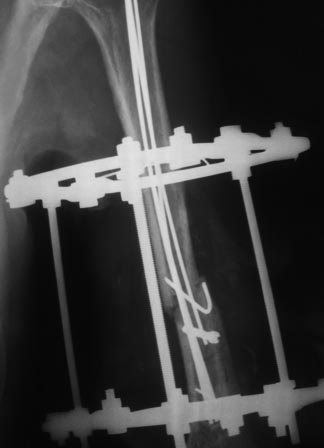

Уважаемые коллеги, прошу прощения за задержку ответа. Операцию проводили 27.11.13г по настоятельной просьбе докторов там, где был оперирован, поэтому пришлось долго ждать контроль.Р-грамму и самого больного, только сегодня приехали. Операция более 4 часов, во время операции установлено полное повреждение лучевого нерва, концы булавовидно утолщены, дефект 2,5-см, с трудом и очень долго пришлось мобилизовать, частично был замурован костной мозолью . Кость укорочена на 3 см, пластика типа русского замка, в это время часть дистального отломка откололась, поэтому пришлось фиксировать винтом, и еще косо спицей., и/м 4-мя спицами, шов нерва, под нервом слой мышца, АВФ из двух колец с компрессией. Р-снимки прилагаются.

P.S. Со слов больного на днях начались периодические стреляющие боли в дистальной части руки.